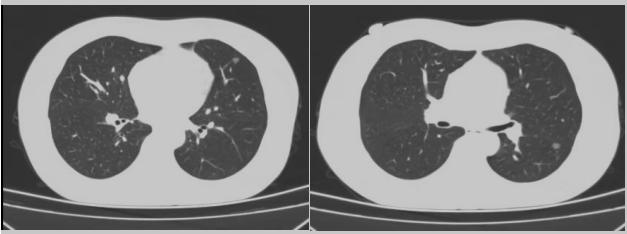

在醫(yī)學(xué)上的定義,肺結(jié)節(jié)就是在肺葉內(nèi)小于等于3公分的結(jié)節(jié)影,密度比正常肺葉要高,周?chē)蟹稳~包裹的,臨床缺乏特異性癥狀和體征,大多數(shù)通過(guò)體檢、特殊人群篩查或者診療過(guò)程常規(guī)檢查及隨診發(fā)現(xiàn)。多發(fā)肺結(jié)節(jié)是指肺內(nèi)存在兩個(gè)或以上直徑均小于等于3cm的病灶,影像學(xué)上常表現(xiàn)為若干個(gè)含磨玻璃影的結(jié)節(jié),近年來(lái)肺部多發(fā)肺結(jié)節(jié)的患者越來(lái)越多,最新統(tǒng)計(jì)數(shù)據(jù)顯示,雙肺多發(fā)結(jié)節(jié)患者占所有肺結(jié)節(jié)患者總數(shù)的18%。

病例二:42歲的范女士,半年前體檢時(shí)發(fā)現(xiàn)雙側(cè)多發(fā)肺結(jié)節(jié),平時(shí)沒(méi)有什么不適。四個(gè)月后再次復(fù)查胸部CT,左上肺及下肺多發(fā)的磨玻璃結(jié)節(jié),其中下葉9mm的結(jié)節(jié)定為高危病灶??吹浇Y(jié)果范女士坐不住了,多方打聽(tīng)慕名找到了市二院院長(zhǎng)王瑾,經(jīng)“肺結(jié)節(jié)MDT”團(tuán)隊(duì)會(huì)診后,決定手術(shù)治療。入院后,胸外科副主任醫(yī)師薛飛詳細(xì)與范女士溝通,并利用Mimics做好了術(shù)前肺部三維重建手術(shù)規(guī)劃,打消了范女士心中的顧慮。經(jīng)過(guò)前期充分準(zhǔn)備后,歷經(jīng)1小時(shí)30分,完成“胸腔鏡下左肺上葉舌段楔切及左肺下葉背段切除術(shù)”,術(shù)后病理檢查結(jié)果確診為左肺微浸潤(rùn)性腺癌。在胸外科團(tuán)隊(duì)的悉心照顧下,患者術(shù)后恢復(fù)良好,一周后順利出院。